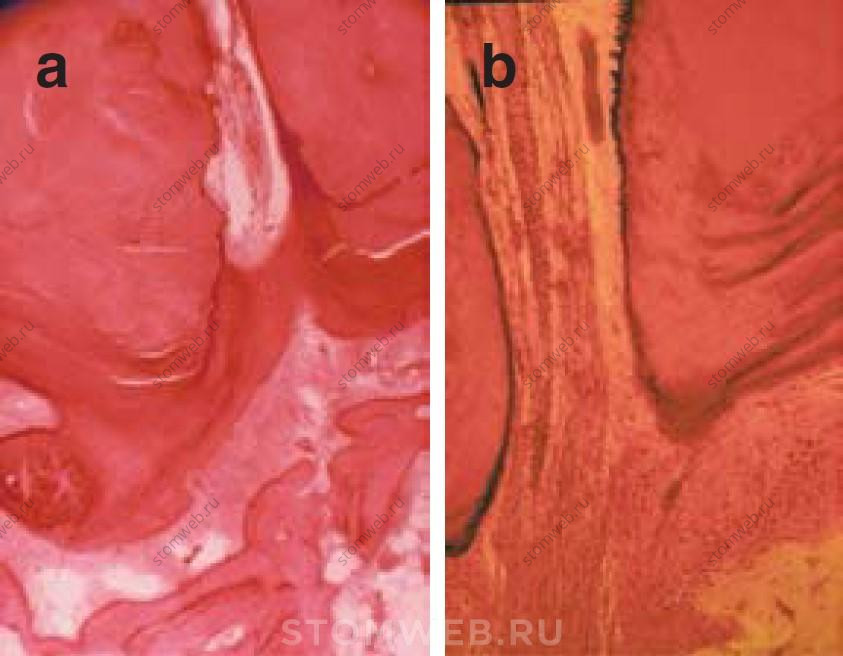

Еще в 1929 году Coolidge написал, что местоположение дентинно-цементного соединения очень сильно варируется, поэтому использовать его как ориентир не имеет особого смысла. У данного соединения очень нечеткие границы, и оно может быть обнаружено на разных уровнях корневого канала (Рис. 1a). Дентинно-цементное соединение может быть обнаружено даже на внешней поверхности корня. Skillen также подчеркивал, что гистологически невозможно определить границу между пульпой с одной стороны и «периодонтальной мембраной» с другой (Рис. 1b).